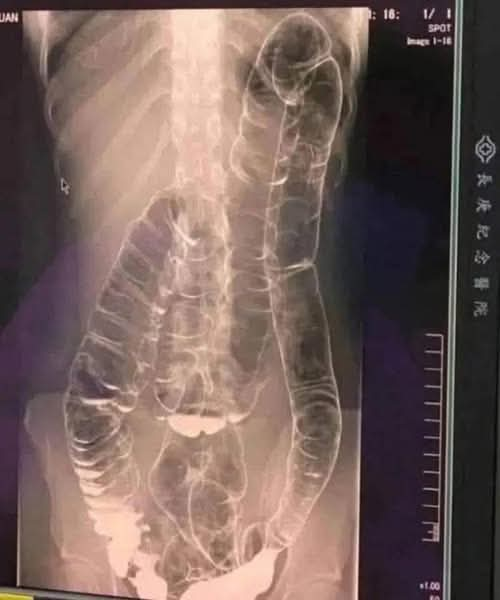

Wie heeft er niet last van constipatie? Dit probleem, vaak als triviaal beschouwd, kan een ware nachtmerrie worden als het chronisch wordt. Dit is precies wat een jonge vrouw overkwam bij wie de overbelaste dikke darm gevaarlijk vergrootte. Dus hoe kunnen we voorkomen dat deze spijsverteringsstoornis verergert?

Bij een onregelmatige stoelgang hopen afvalstoffen zich op in de dikke darm. Dit leidt tot extra druk die pijn, een opgeblazen gevoel en in ernstige gevallen ernstige complicaties kan veroorzaken.